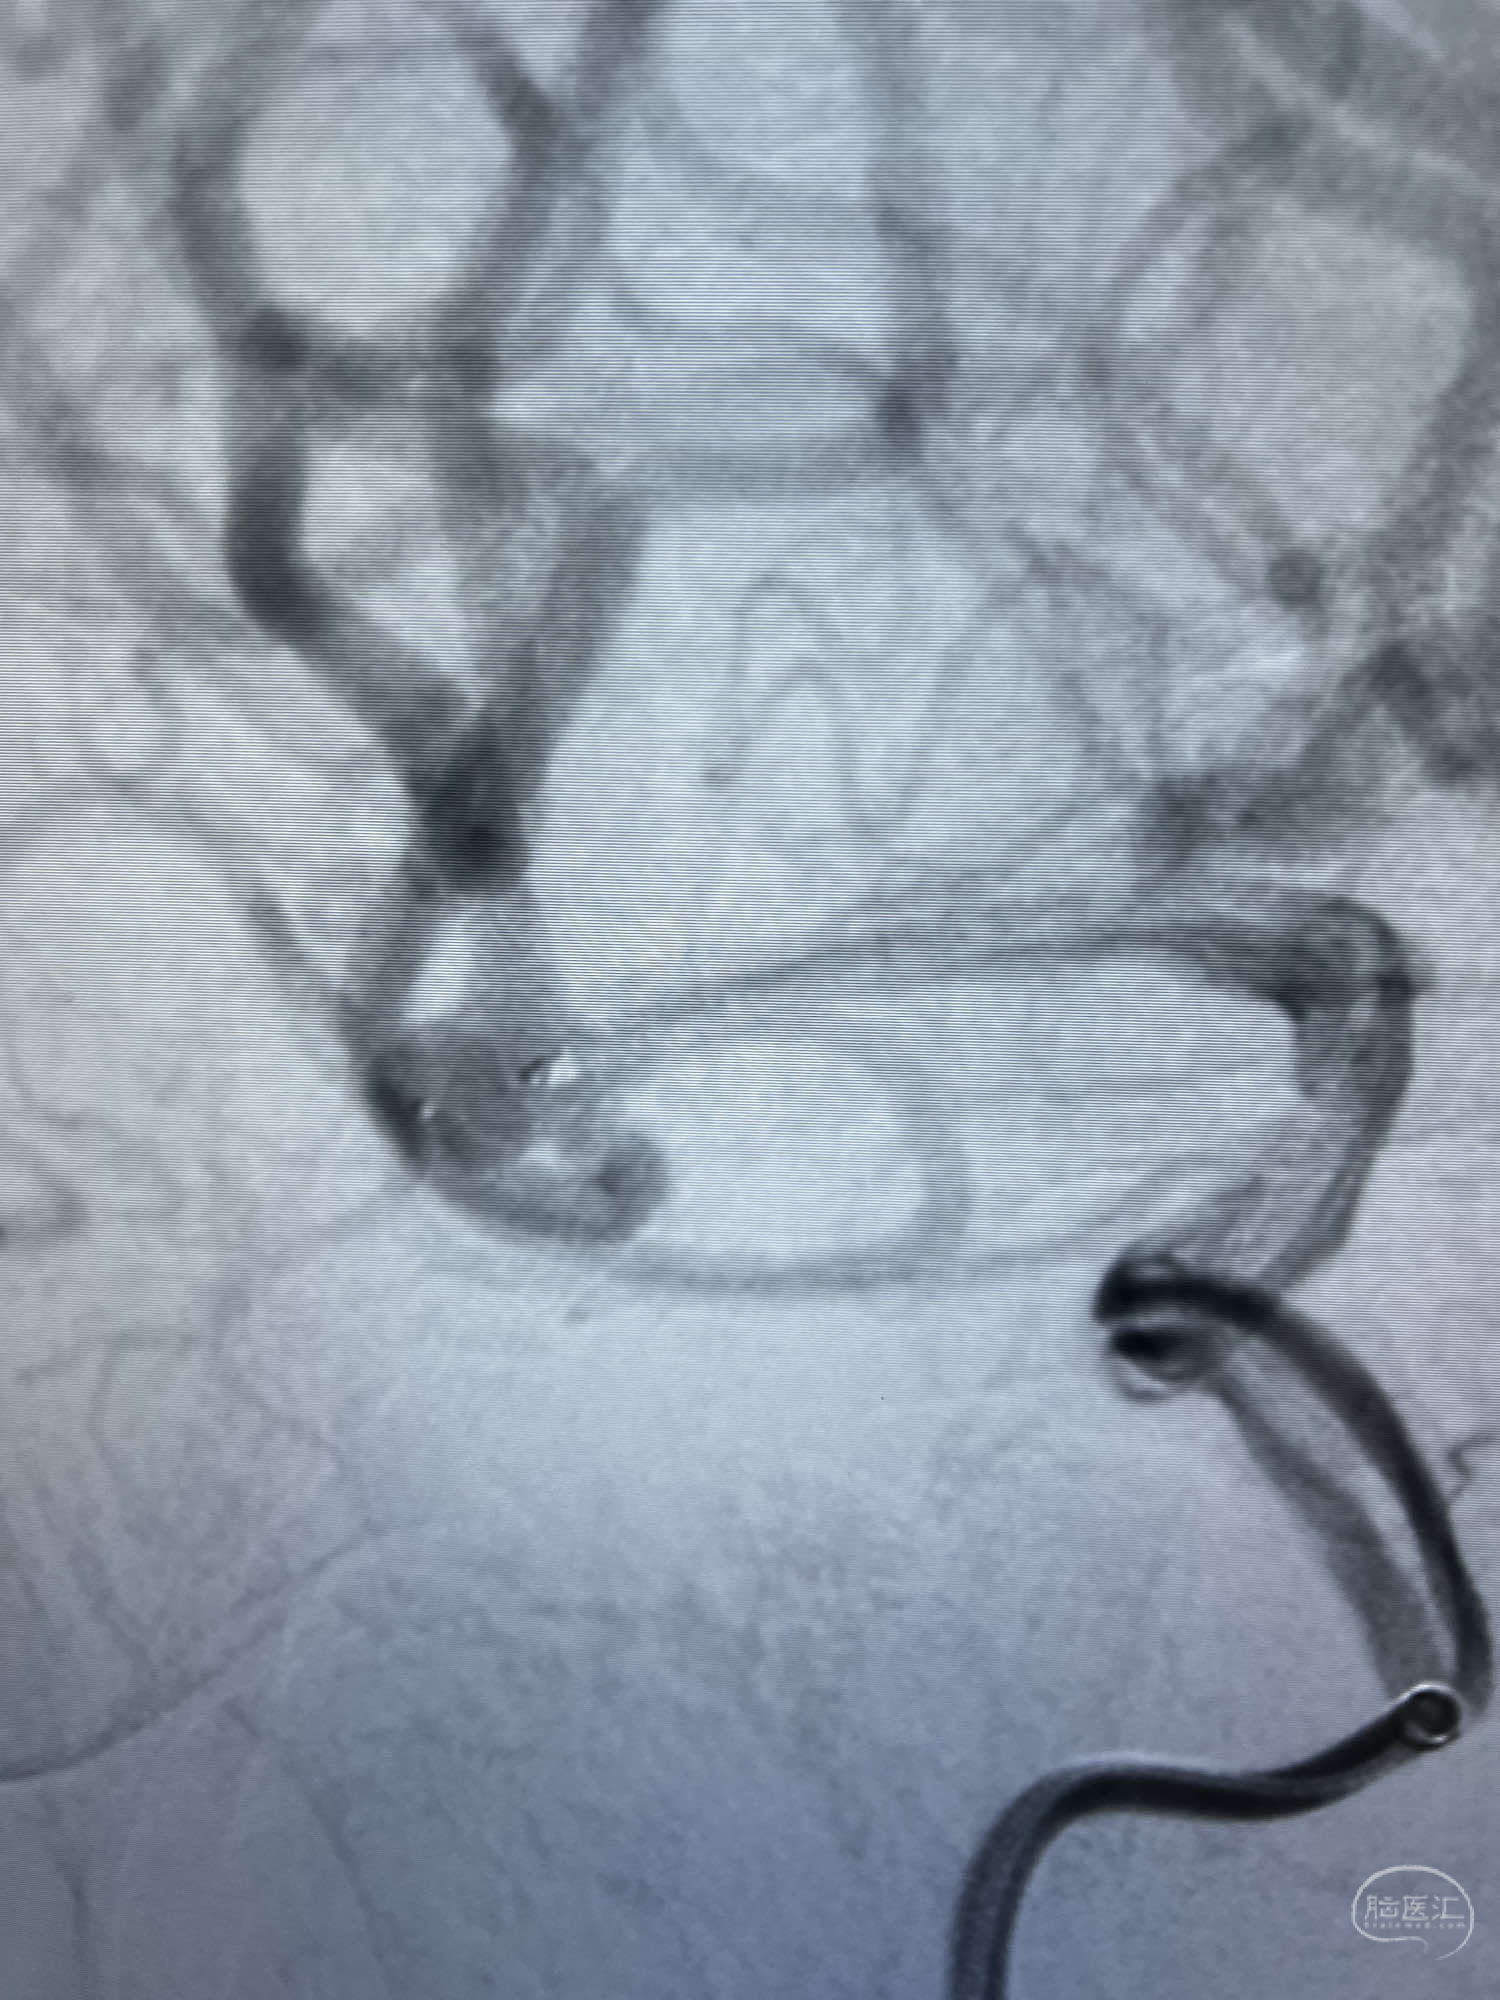

6F Neuromax➕6F115cm 心玮中间导管建立路径,sychro14微导丝➕VIA21超选至动脉瘤体内近中部,WEB5mmx3mm植入动脉瘤。

WEB瘤内扰流装置5mmx3mm经过“种子、萌芽、开花”三个阶段,打开后良好贴壁,动脉瘤内血液滞留,载瘤动脉通畅。WEB一步到位,通过瘤内扰流的方式起到栓塞动脉瘤的作用,避免了应用支架保护分支血管,简化了操作步骤,降低了术中血栓及出血的风险。